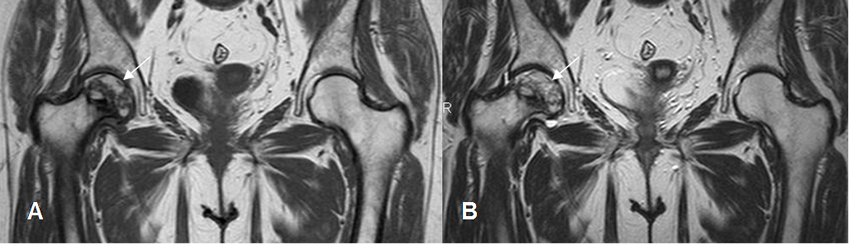

Fig 82. Osteonecrosis.

A y B: RM coronal en T2. Signo del doble halo. Reborde hiperintenso en T2, específico de osteonecrosis.